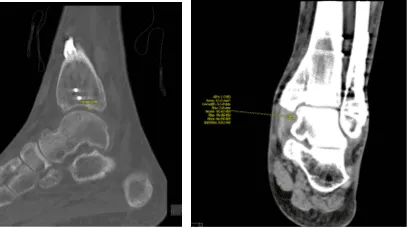

Para una revisión más detallada de la condición del tobillo, acordamos realizar un TAC. El resultado mostró fractura trimalleolar cicatrizada tras ORIF, con placa y tornillos en el peroné, y el maléolo medial con una deformidad leve con un paso de 1 mm en la superficie articular en el plafond tibial medial.

Deformidad leve en el margen anterior de la palma tibial. No hay nuevas fracturas. Hemos decidido realizar fisioterapia formal así como un programa de ejercicios en casa para la rehabilitación de la rodilla. Los pacientes seguían regularmente una visita a la consulta cada 3-4 semanas. El paciente se recuperó bien tras la cirugía y continuó la fisioterapia.

TAC – Tobillo izquierdo sin contraste